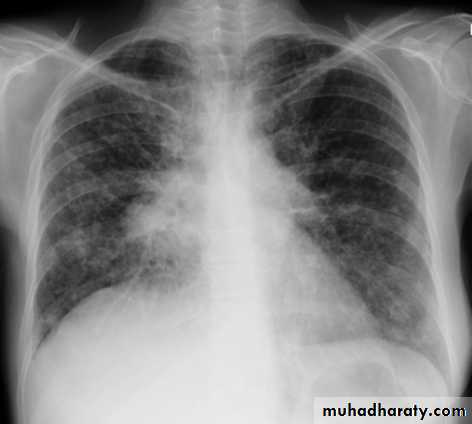

Lobular consolidation ( broncho or lobular pneumoniaCXR of adult ,PA and lateral views show:Patchy consolidation in both lung fields (diffuse) mainly in the lower zonesNormal heart size

Very important to consider that pulmonary edema in normal sized heart have close similar appearance to broncho pneumonia

The important Golden Key differentiation is the cardiac size being enlarged in pulmonary edema .